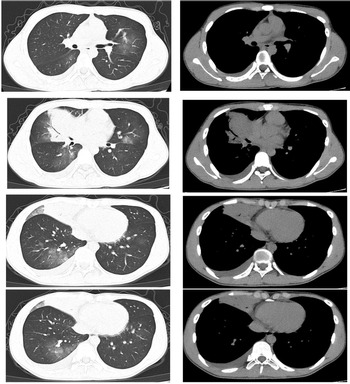

The patient was a 16-year-old male. He started to have fever 7 days prior to visiting our clinic. His maximum temperature was 39.9 °C. He also presented with a cough and white phlegm. The patient visited our emergency department on the second day of disease onset. The lung CT scans revealed ‘right middle lobe medial segment inflammation and consolidation’. The results of a routine blood test were: leukocyte count 5.3 × 109/l, neutrophil count percentage 78.6%, neutrophil count 4.17 × 109/l, lymphocyte count 0.65 × 109/l, CRP 21.28 mg/l. The patient's condition did not improve after self-administration of arbidol and cefdinir. The patient was subsequently treated with ceftazidime and an intravenous infusion of azithromycin, but his condition was still not alleviated. A routine follow-up blood test 7 days after disease onset revealed the following: leukocyte count 9.8 × 109/l, neutrophil count percentage 87.6%, neutrophil count 8.54 × 109/l, lymphocyte count 0.86 × 109/l, CRP 82.80 mg/l. The lung CT scans (Fig. 2) showed right middle lobe inflammation and expanded areas of consolidation, new signs of inflammation in multiple lobes bilaterally and bilateral (mainly right-sided) pleural effusion. The patient was admitted to the ward for further treatment.

Fig. 2. Chest CT of case 2.

Physical examination on admission: T: 37.7 °C, P: 80 beats/min, R: 18 breaths/min, BP: 97/67 mmHg. Harsh breathing sounds were detected in both lungs. No dry or moist rales were heard. Physical examination of the heart and abdomen showed no conspicuous abnormalities. The results of a blood gas analysis without oxygen therapy were as follows: pH 7.46, pCO2 24 mmHg, pO2 74 mmHg, HCO3 6.8 mmol/l, Lac 1.56 mmol/l, SO2c 95%. Pathogen testing on pharyngeal swabs obtained from the patient was positive for adenovirus DNA and negative for respiratory syncytial virus RNA, influenza A and B nucleic acids, and novel coronavirus nucleic acids. The combined antigen/antibody test for HIV and blood or sputum bacterial culture was negative. Testing for mycoplasma IgM was positive, but DNA testing for mycoplasma pneumoniae based on pharyngeal swabs was negative. The patient was administered the antiviral ribavirin and the antibiotic azithromycin. He recovered and was discharged after 10 days.